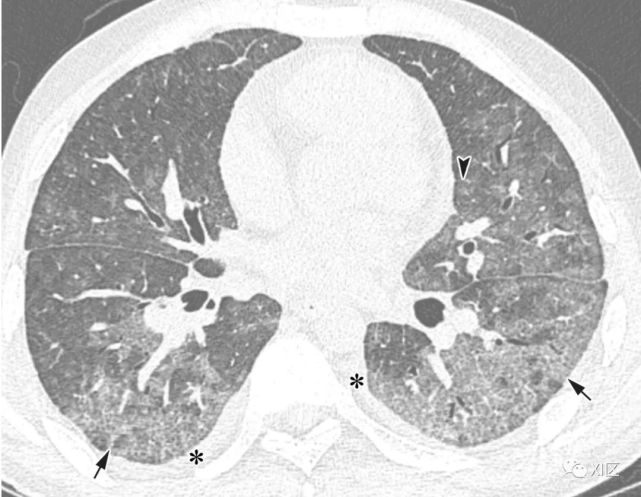

图13 63岁的男子,原发性中枢神经系统淋巴瘤化疗后合并发热,诊断为人博卡病毒肺炎

(上)胸部X线片显示两肺均弥漫性不规则斑块状实变(箭)和GGO。在同一天获得的轴位薄层(1mm)胸部CT图像显示,沿着支气管血管束和肺部周边区域出现不规则的斑块状实变(箭),支气管壁增厚,小叶间隔增厚 (箭头),伴有少量双侧胸腔积液(*)。

Koo H J , Lim S , Choe J , et al. Radiographic and CT Features of Viral Pneumonia[J]. Radiographics, 2018, 38(3):719-739.